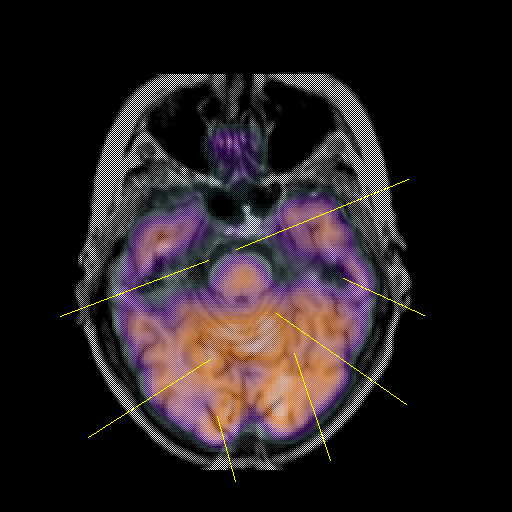

overlay: Slice 17

Slice 17

Unlabeled

Pointers

Labeled